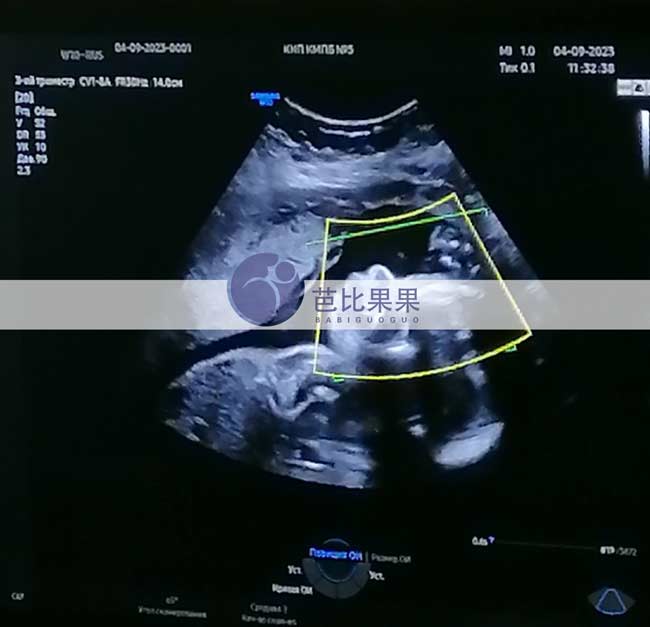

L先生的乌克兰试管妈妈做四维彩超检查,胎儿数据正常

L先生家的乌克兰试管妈妈到医院做了四维彩超检查,胎儿身体各项数据都发育正常,彩超下可见宝宝很活泼~